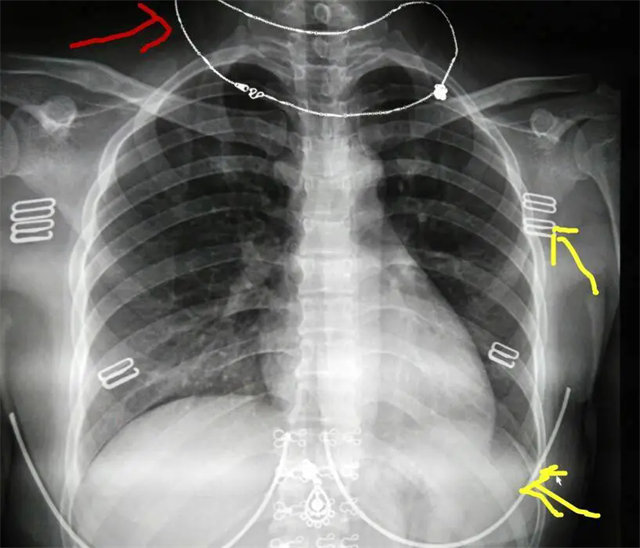

缺陷:雙側(cè)胸鎖關(guān)節(jié)不對(duì)稱(chēng),且有手機(jī)顯影。

解決:去除手機(jī)后,使患者左側(cè)緊貼成像件曝光。